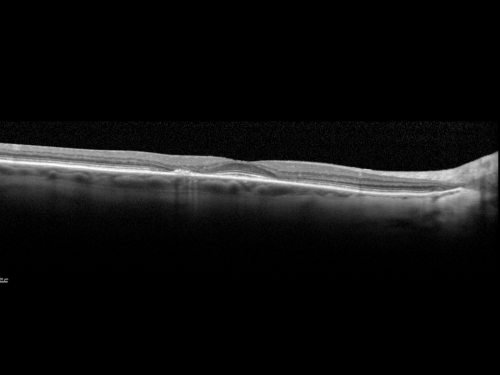

Plaquenil Toxicity both Eyes - Partial Bull's Eye - Discontinued 6 Years ago SD-OCT (Spectral domain optical coherence tomography)

82-year-old woman was on Plaquenil from 1976 from 2005, 200 mg a day.  It was discontinued because of abnormal visual fields 6 years ago. OD 20/32,  OS 20/40